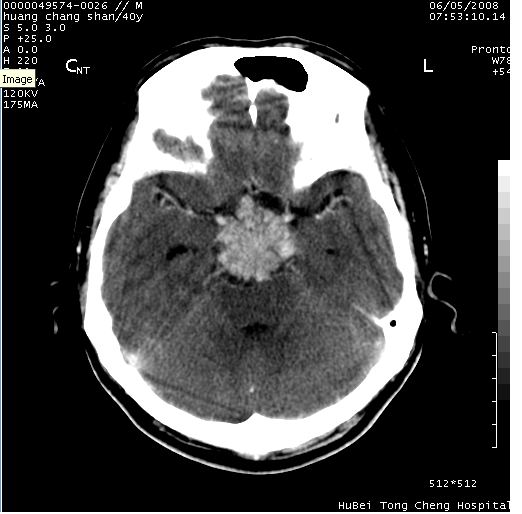

患者 m,40y。头痛,视力模糊,多饮多尿,性欲减退半年余。

行ct平扫+增强,图象如下:

鞍背无破坏和明显受压,病变明显均匀强化,边界清晰。鞍上区脑膜瘤可能性大,不除外生殖细胞瘤。

鞍上池肿瘤,鞍背及垂体窝形态变化不明显,病灶强化密度均匀且高度强化,考虑实性颅咽管瘤、生殖细胞瘤及脑膜瘤可能。

结合临床考虑鞍上生殖细胞瘤可能性大于脑膜瘤(增强未见脑膜围征),建议结合冠状位扫描看病灶起源及垂体窝、鞍底情况。垂体窝内未见明显软组织密度影,垂体窝未见扩大,暂不考虑垂体瘤;病灶较大,未见囊变及钙化,颅咽管瘤不支持。期待结果!

2、ct表现:肿瘤呈类圆形,均匀略高密度,无囊变,无钙化。侧脑室有扩大。

5、友情提示:下回发现鞍区占位性病变,最好加扫冠状位,了解肿瘤与蝶鞍的关系及蝶鞍骨质的改变。